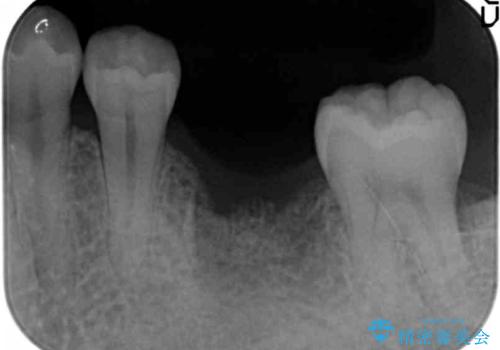

- 「長年虫歯放置した結果、抜歯となってしまった左下奥歯に歯を入れたい」、と希望され来院されました。

前後の歯は虫歯も治療歴もないため、前後の歯を削らなくてはいけないブリッジではなくインプラント治療による咬合機能回復を計画します。

減ってしまった顎骨に増骨処置を行うことで、より安定した環境で長く使用できるようなインプラント治療を行っています。